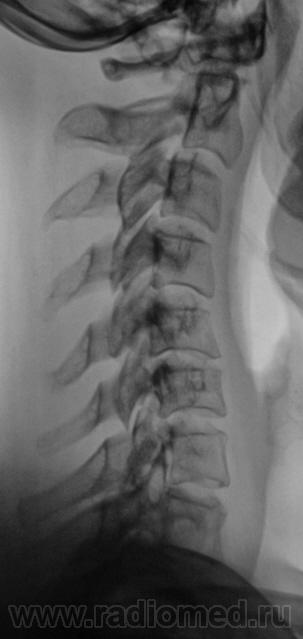

Я в протоколе, отметил нарушение статической функции в виде формирования патологического кифоза, отметил антелистез С2, С3, а также указал, что "это" свидетельствует о нестабильности в сегментах С2-С3, С3-С4.

У данной пациентки - выраженное нарушение статики, а значит смело можно писать дискоз + снижение высоты межпоз. диска в С5-С6 позв. сегменте = остеохондроз.

1.Касаемо остеохондроза С5-6 - вне всякого сомнения и...не вчерашний.

3. Касаемо нестабильности в в\шейном отделе, мне кажется - надумано, тем более, что хотим мы или не хотим, целый ряд специалистов указывают на допустимую нормальную подвижность в пределах 0,3 см максимум.

4. Касаемо ретролистеза С6 - вне всякого сомнения, ибо до 0,4 см...если не немного больше.

нарушение статики ШОП в виде кифоза, признаки остеохондроза и ункоартроаза.

2. Кифотическая деформация (она же функциональная установка по Игорю Ивановичу, она же - анталгическая - по Валетнину Львовичу, что, впрочем, одно и то же по сути)-вне всякого сомнения....но она же - предупреждение о клиническом ухудшении; кстати - если придираться, то и кривошея влево, хотть и умеренная, но есть, более чем уверен, что из той же оперы.

5. Поход к мануалисту и наличие кифоза, ретролистеза С6, кривошеи, поворота среднешейного отдела вокруг вертикальной оси, хоть и легкого, но имеющегося, приводят к мысли, что имеет место подвывих в одном из дугоотростчастых суставов в пределах С4-С7....вот только вопрос - какого...вот он то и привел к обострению клинической ситуации с остеохондрозом....не вчерашним....